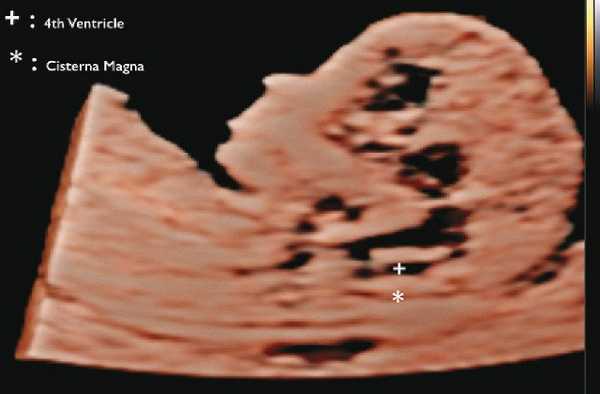

В прошлом лечащие врачи и врачи ультразвуковой диагностики проводили ультразвуковой скрининг для выявления дефектов нервной трубки, главным образом открытого расщепления позвоночника (spina bifida), во II триместре. В последние годы предложены ранние ультразвуковые маркеры на 11-14-й неделе беременности (внутричерепное пространство, использование БПР и соотношения БПР/ПРЖ (поперечный размер живота)), которые позволяют выявить у некоторых плодов высокий риск открытого расщепления позвоночника (рис. 7) 10.

Рис. 7. Внутричерепное пространство при ультразвуковом скрининге по поводу открытого расщепления позвоночника.